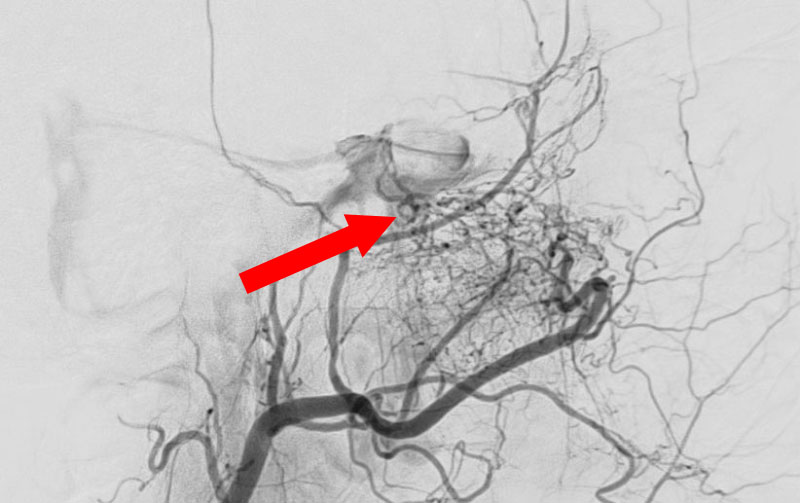

'25年10月

硬膜動静脈瘻

50代

救急外来

No.1591 手術前

No.1591 手術中

No.1591 手術後